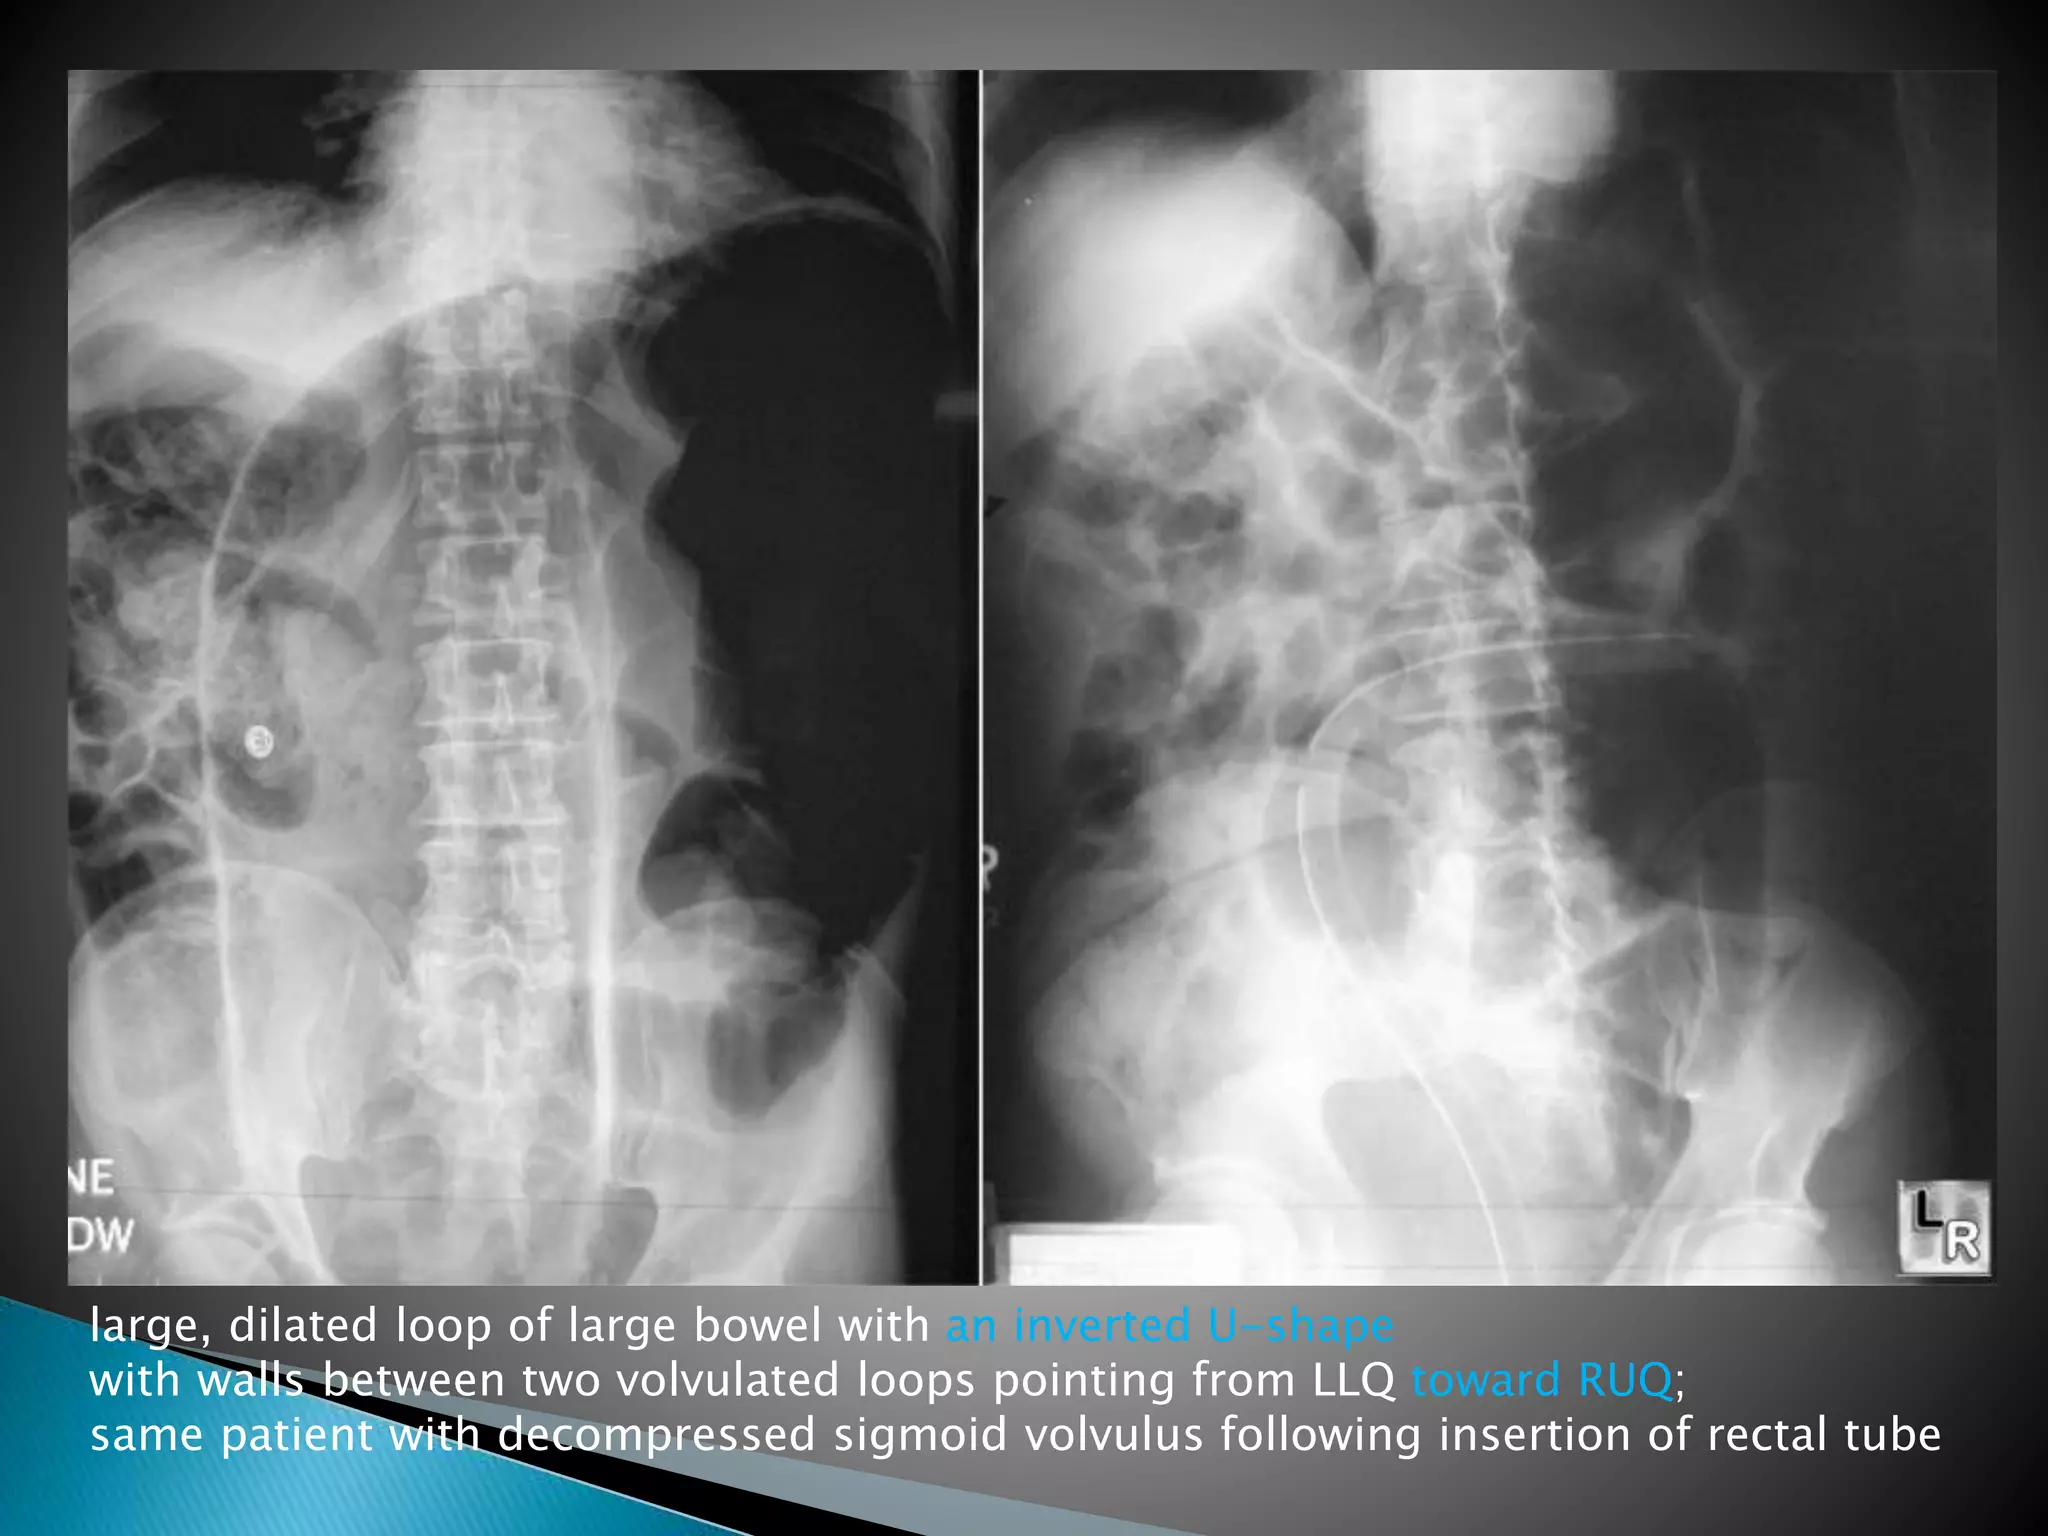

Inverted U-shaped appearance of distended

sigmoid loop

 Largest and most dilated loops of bowel are

seen with volvulus

 Loss of haustra

 Coffee-bean sign à midline crease

corresponding to mesenteric root in a greatly

distended sigmoid

 Sigmoid volvulus – bowel loop points to RUQ

large, dilated loop of large bowel with an inverted U-shape

with walls between two volvulated loops pointing from LLQ toward RUQ;

same patient with decompressed sigmoid volvulus following insertion of rectal tube

 Diagnosis Abdominal plainfilms usually diagnostic Inverted U-shaped appearance of distended sigmoid loop  Largest and most dilated loops of bowel are seen with volvulus  Loss of haustra  Coffee-bean sign à midline crease corresponding to mesenteric root in a greatly distended sigmoid  Sigmoid volvulus – bowel loop points to RUQ

large, dilated loopof large bowel with an inverted U-shape with walls between two volvulated loops pointing from LLQ toward RUQ; same patient with decompressed sigmoid volvulus following insertion of rectal tube